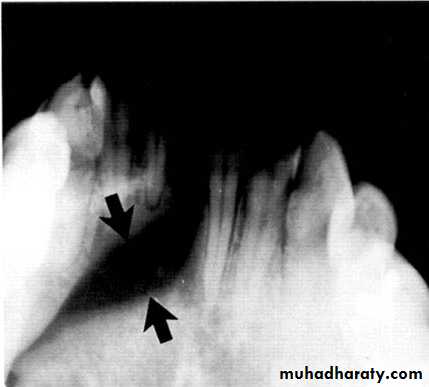

Radiolucency at apex of endodontically treated tooth

A: Radiolucent apical scar left after successful endodontic treatment..

B:New bone forming from the periphery of theLesion.

If the R.L.enlarged, pain,sinus,or no regression in the size of lesion after 6months (P. A. Cyst).

Apical scar